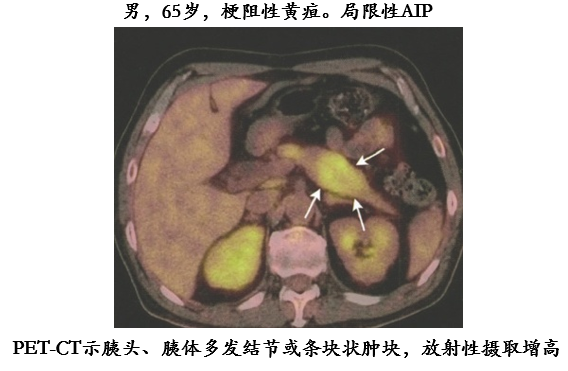

PET-CT

18F-FDG PET-CT 检查实现了解剖与功能代谢影像的融合,一次检查全身成像,在显示胰腺改变的同时,还可以发现胰腺外组织或器官受累情况,在疾病的诊断和全身评估中具有优势;对于治疗后的疗效评估也具有价值。

PET-CT 表现:病变部位出现 FDG 摄取增高,延迟后摄取进一步增高。摄取值增高与炎性细胞浸润吞噬有关。高摄取灶的形态与病变范围一致。

引用自:Rauscher et al. European Journal of Hybrid Imaging (2017) 1:11